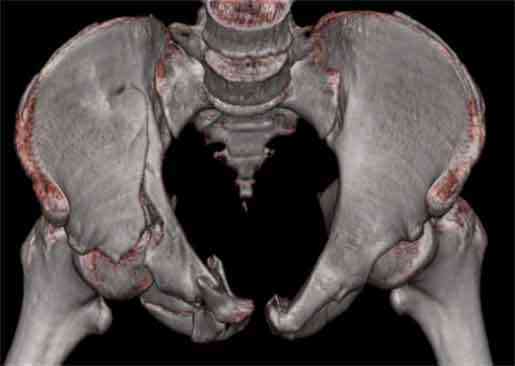

Не смог разглядеть на представленных картинках частичное повреждение левого КП, повреждение Денис1-2 справа? 3Д реконструкции в инлет и боковой проекциях убедительно не демонстрируют типа повреждения задних отделов тазового кольца(справа боковая масса скомпремирована), Наверное, у тебя есть возможность оценить тип перелома крестца по прямой проекции 3Д.

Насколько я понял из твоего письма, обращенного к анонимному vit, ты не видишь показаний к реконструкции перелома. Я бы взялся за реконструкцию(илео-ингвинальный доступ), хоть прошел и месяц после травмы: боковая 3Д показывает смещение нагрузочной зоны впадины, что однозначно будет способствовать разрушению хряща головки и впадины( особенно у 16 летнего пациента с ожидаемым высоким уровнем активности) + изменение геометрии впадины за счет неустраненного смещения фрагментов колонны (КТ, 3Д данные).

На мой взгляд, без реконструкции этот сустав обречен (концепция вторичной конгруэтности в данных условиях работать не будет), реконструкция дает шанс на восстановление функции сустава.

Сравнивая боковые проекции 3Д реконструкций, разница переломов очевидна: в предыдущем случае на боковой проекции не видно было ступени нагрузочной зоны суставной поверхности - это и объясняет приличную функцию сустава.

В данном случае 3D и корональные срезы КТ менее информативны, чем поперечные. Согласен с левосторенним минимальным повреждением КПС, но не смог уловить перелом крестца.

На 3D по линии перелома ацетабулум возможно сверху в подздошной кости уже есть сращение? или состояние перелома у молодых, после неполного (при пластической деформации) перелома.

По представленным материалам, мне кажется, перелом был передней колонны ацетабулум с минимальным вовлечением нагрузочной поверхности сустава, левосторенний повреждение КПС и лонных костей.